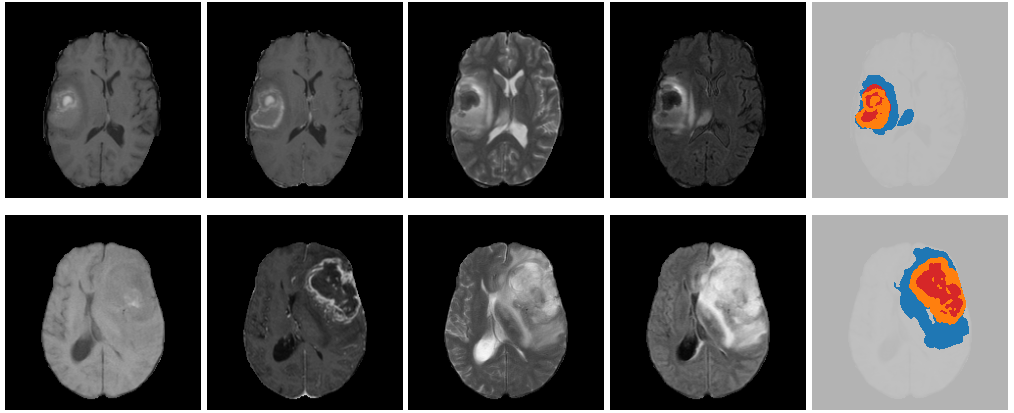

In the domain of biomedical segmentation, a significant effort has been made regarding glioblastomas. It is the most common brain tumor, diffuse, of variable degree of aggressiveness, and whose medical prognosis is difficult to establish. Its segmentation involves three regions: the peritumoral Edema (ED), composed of invaded tissue; the Tumorous Core (TC), representing the primary tumor mass; and the Enhancing Tumor (ET), usually the surgical target, along with the necrotic portions of the tumor. Their union is the Whole Tumor (WT), the entirety of the disease (Fig. 2).

2.1.2 Myocardium

In clinical cardiology, it is essential to measure cardiac functions, such as volumes, mass of the ventricles, or thickness of the myocardium [40, 6]. These measurements are commonly obtained from segmented Cardiac Magnetic Resonance Imaging (CMR), which are multi-slice 2D MRIs, typically segmented in three classes: myocardium (Myo), left ventricular cavity (LV) and right ventricle (RV) [15, 10, 11], shown in Fig. 3.

To date, only a few datasets are publicly available [13]. The first one was the Fetal Tissue Annotation and Segmentation Dataset (FeTA) [41, 42], led by the University Children’s Hospital Zürich and the University of Zürich, which gathered 50 manually segmented pathological and non-pathological fetal brain MRIs, across a range of gestational ages (20 to 33 weeks). On the other hand, a number of atlases are found online, such as the Spatiotemporal Atlas (STA) [43]. It contains representations of the average fetal brain, at one-week intervals between 21 and 38 weeks gestational age (Fig. 4). These images were obtained via diffeomorphic deformable registration of 81 T2-weighted MRI scans of healthy fetuses. As opposed to the clinical dataset FeTA, atlas data are smoother and easier to work with, and will be employed in this article.

In this article, we invoke PH to devise a general train-free framework for MRI segmentation, and demonstrate its use on concrete datasets. It is divided into three simple modules: (1) identification of the whole object to segment; (2) detection of a particular subset; and (3) deduction of the other regions. The second step involves prior morphological knowledge, presenting a topology that PH can detect. We validate our framework on three segmentation problems: glioblastoma from brain MRI, for which we take advantage of the spherical shape of the Enhancing Tumor; cardiac segmentation from Cardiac Magnetic Resonance Imaging (CMR), based on the cylindrical shape of the myocardium; and cortical plate from fetal brain MRI, using the fact that it forms, in cortical slices, one or two circles (see Fig. 1).